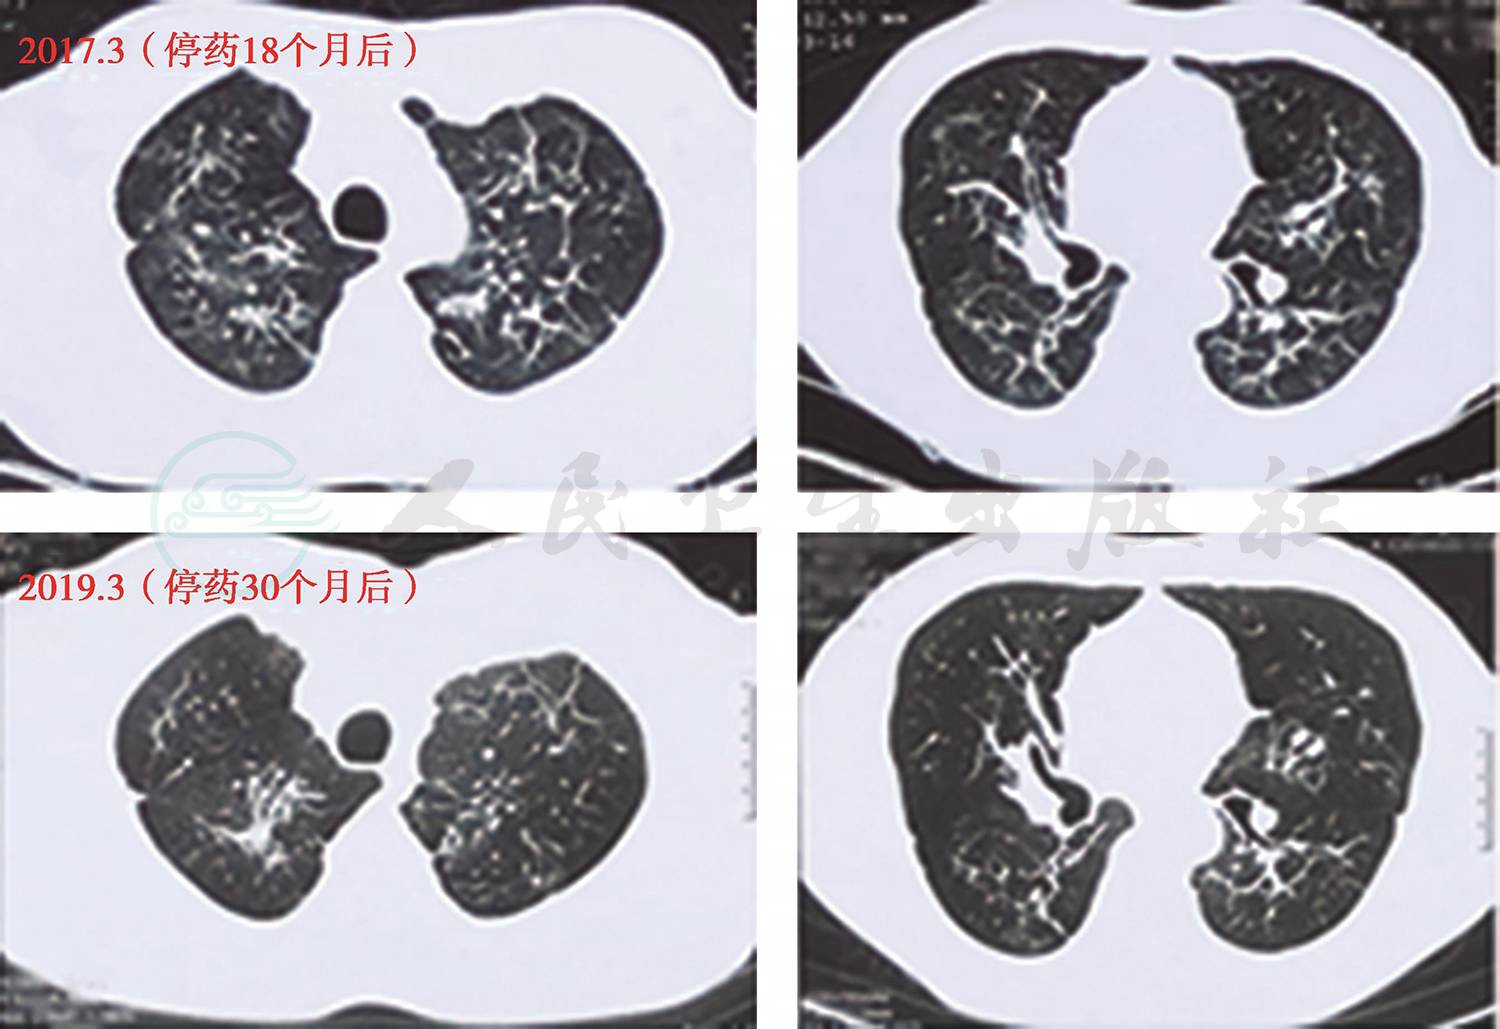

(二)随访

患者抗真菌治疗后,咳嗽、呼吸困难等症状明显缓解,肺部影像学病变明显好转(图6)。随访4年,患者除仍有轻微咳嗽外,无其他呼吸道相关症状。

图6 出院后随访CT

(CT时间包括2015年1月、2015年3月、2015年9月、2016年3月、2017年3月、2019年3月)